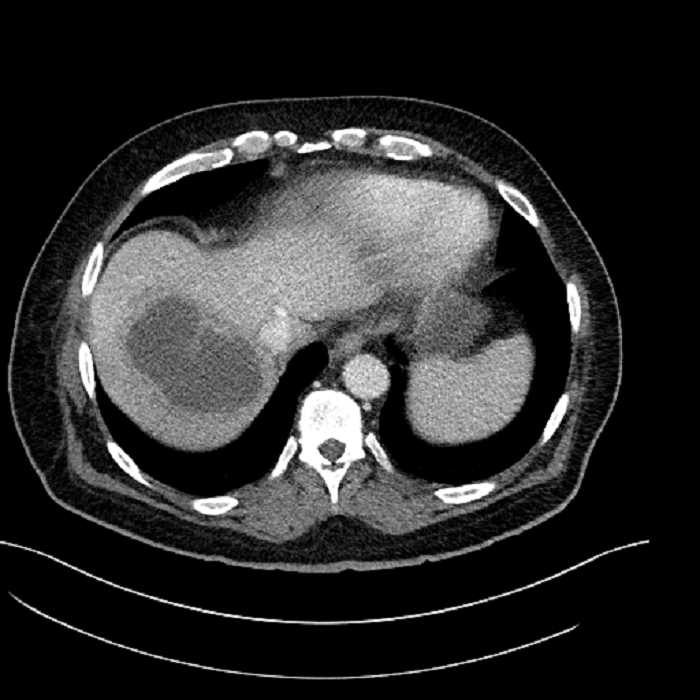

• Large fluid density structure in hepatic segments 7 and 8 measuring 10 x 7 x 7 cm with internal septation and circumferential ill-defined low density compatible with edema

• Peripherally enhancing subcapsular collections along the anterior margin of the left hepatic lobe measuring 3 x 1 cm and 2 x 1 cm

• Clearly marginated fluid density structure in segment 7 and several other scattered tiny hypodensities, which likely represent cysts

• Hepatic abscess

Acute sigmoid diverticulitis complicated by a small contained perforation and a large abscess in the right hepatic lobe. Additional small subcapsular abscesses along the anterior margin of the left hepatic lobe.

• The classic CT imaging appearance is a double target sign with internal low density surrounded by an internal enhancing rim (capsule) and a low density external rim (edema)

Hepatic abscess showing the double target sign with low density internally surrounded by a thin inner enhancing rim (red arrow) and ill-defined outer low density rim (yellow arrow). Blue arrow indicates an internal septation. Red arrows: additional smaller subcapsular abscesses. Red arrow: focal contained perforation associated with diverticulitis.